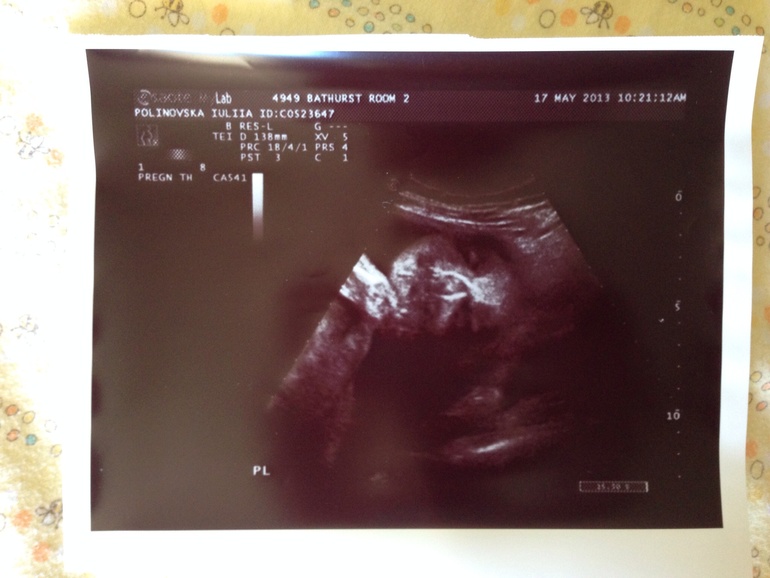

17.05.13 узи. Последнее наше узи. Плацента встала на место - это хорошо. Но нас озадачили, на узи была другая женщина и она сказала, что ей больше похоже на мальчика, но ребеночек очень двигается и она отправит запрос экспертам (или кому ...) и они результаты уже врачу переправят.

Сказать честно я немного расстроилась. Я уже свыклась с девочкой, мы уже и имя придумали и по имени обращались к пузожителю, хотя какой то червь сомнений жил во мне все равно. А еще было очень забавно, потому что во время узи, крошка был очень активный и толкал ту штучку которой узи делают.